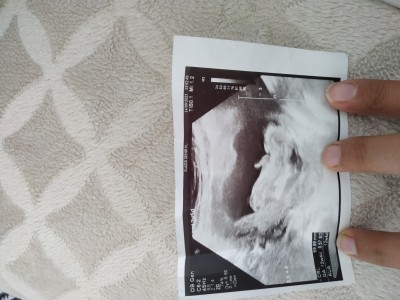

Kızlar bugün ikili taramaya girdim fakat cinsiyet söylemediler tahmin yapabilen var mı? (kese sol tarafta)

Gebelik haftası 12+4